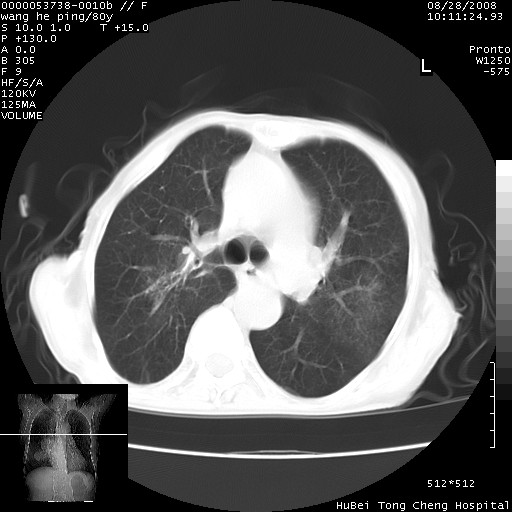

以下是引用黑白光影在2008-8-28 22:33:00的发言:[br]右肺中央型肺癌伴阻塞性肺炎,肺癌肺转移。

以下是引用lshx在2008-8-28 22:06:00的发言:[br]1.右肺中心型肺癌伴阻塞性肺炎,不除外双 肺早期转移。[br]2.心包积液。

以下是引用随光逐影在2008-8-29 7:40:00的发言:[br]1)右肺中心型肺癌伴阻塞性肺炎,肺内转移。2)心包积液(少量)。

以下是引用wqs571018在2008-8-28 21:56:00的发言:[br]右肺中心型肺癌伴阻塞性肺炎可能。

以下是引用liuyue在2008-8-28 22:46:00的发言:[br]1.右肺中心型肺癌伴阻塞性肺炎。[br]2.心包积液(少量)。